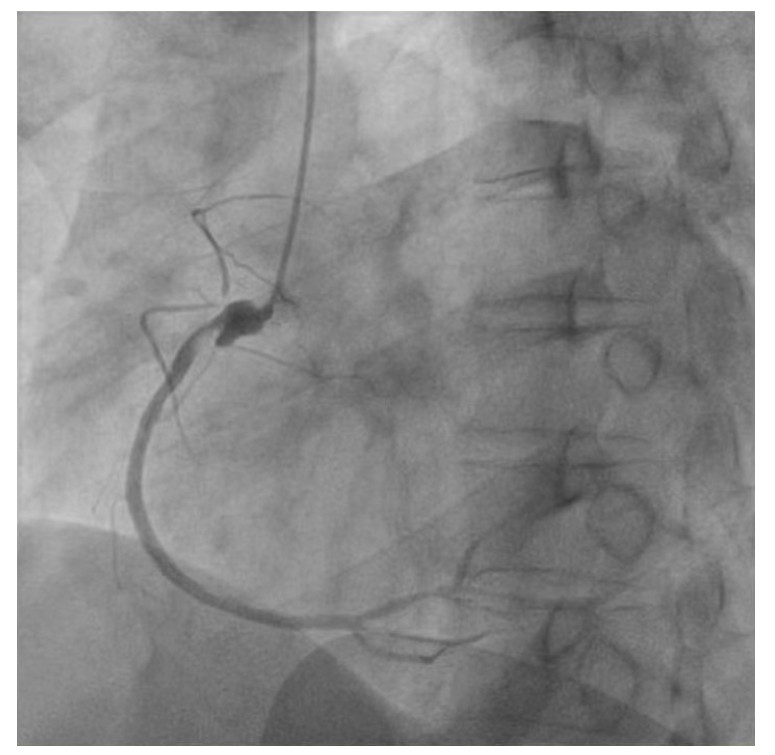

| 图 2 患者冠脉造影示右冠外伤性动脉瘤伴狭窄 |

对于严重创伤活动性失血患者出现心脏骤停是否进行ECPR抢救目前尚有争议[1]。本例患者病情严重且复杂,胸腹联合损伤,肝脏及肠系膜挫伤,创伤活动性失血合并心肌顿抑和冠脉损伤,并频繁出现心脏骤停,如何思考与平衡救治中的矛盾有较大的难度。最终救治团队决定对患者进行ECPR救治主要基于以下判断:①创伤性心脏骤停(TCA) 最常见原因为大量出血, 缺氧, 张力性气胸, 心包填塞等,对该患者心脏骤停原因进行5H5T分析,患者的心电图表现呈现下壁心肌梗死的表现,提示可能合并右冠的损伤,这也可能是患者出现心脏骤停的最大原因,并且该原因具有可逆性;②患者入院时有明显的休克表现,BP 52/31 mmHg,Lac 6.3 mmol/L,但结合患者心率78次/min,首次HGB 146 g/L,同时CT未见大量胸腹腔积液及骨盆骨折,而心电图示明显的ST-T改变和胸导联低电压,故患者此时考虑失血性休克可能性较小,而心源性休克的可能性更大;③结合患者心脏彩超及肌钙蛋白表现,患者入院后顽固休克的主因考虑为心肌挫伤、心肌顿抑导致,同样具有可逆性;④患者有活动性失血但尚在可控范围内,上机前最后一次复查HGB为95 g/L,尚可通过输血等措施维持。相比于不使用的毫无机会,ECMO的救治能为该患者带来一线生机。患者最终的结局也验证了上述判断的正确性,冠脉造影示右冠外伤性动脉瘤伴狭窄,考虑为患者心脏骤停的根本原因,但这也极其罕见,笔者检索了相关文献数据库,未见有类似的报道。